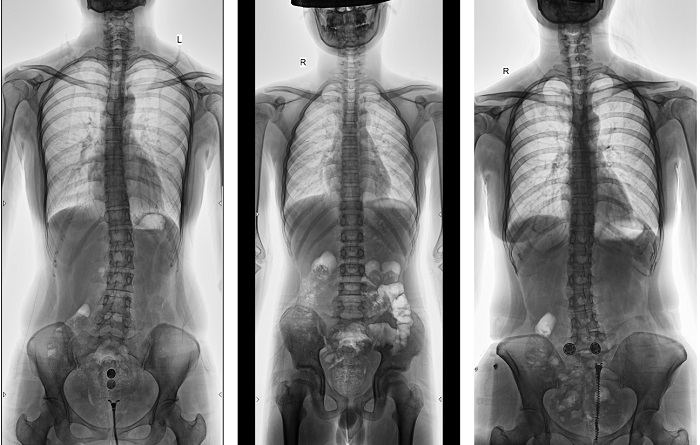

動態(tài)DR全景拼接功能突破平板尺寸長度限制,可進行立臥位攝影,對脊柱、下肢及下肢靜脈造影進行分段攝片,然后對分段圖像進行拼接,在一幅X光圖像上完整顯示全脊柱或下肢整體形態(tài),獲得全脊柱或全下肢圖像,有效解決了傳統(tǒng)X光片不能一次成像問題,通過直觀顯示脊柱和下肢的整體解剖形態(tài)及側(cè)凸部位,為臨床治療提供重要參考依據(jù)。

▲全脊柱DR影像

普利德多功能動態(tài)DR進行全脊柱全下肢圖像拼接時,影像密度均勻、清晰、接緣處過渡自然,圖像質(zhì)量高,完全能滿足臨床觀察、診斷及測量要求。拍片過程也更加方便快捷,使患者得到快速診斷,及時治療,為臨床醫(yī)生和患者帶來更大的便利,大大助力醫(yī)院醫(yī)療服務(wù)能力的提升!